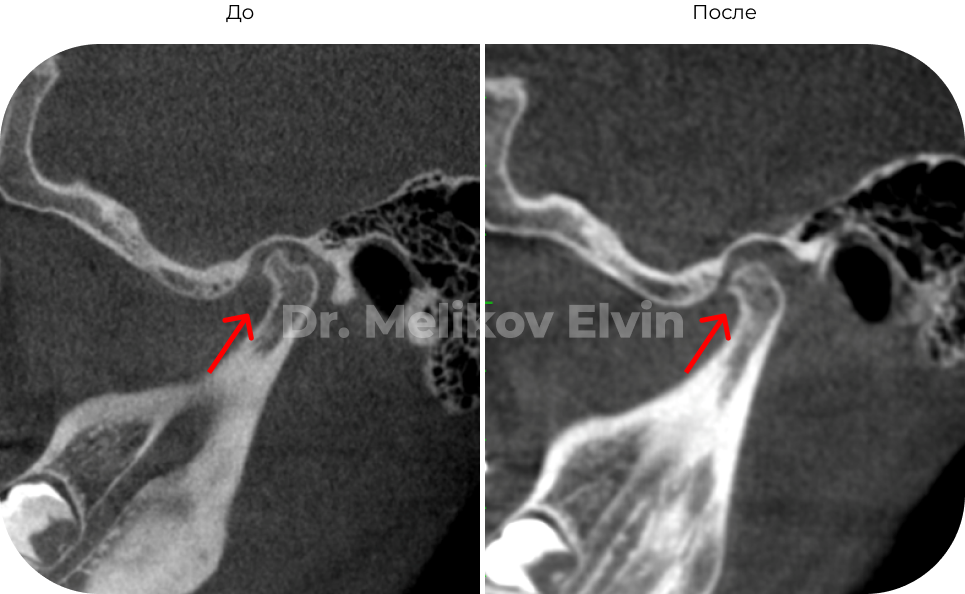

Компьютерная томография ПОСЛЕ.

После реабилитации.

Суставной диск репонировался: позиционирован на головке мыщелкового отростка.

Декомпрессия в суставе, восстановилась трофика и целостность кортикальной пластинки.